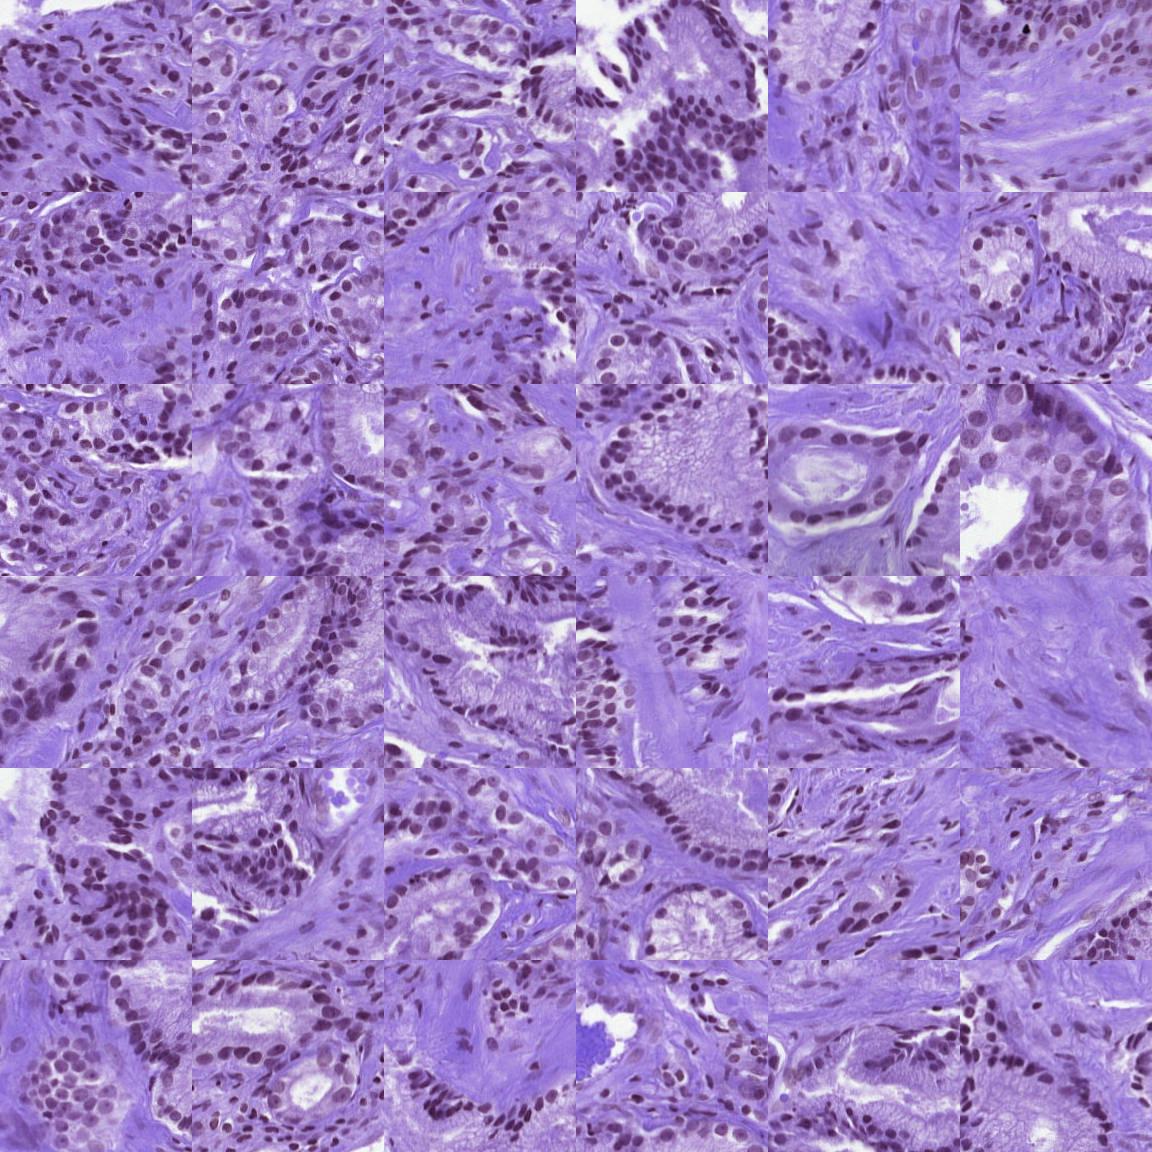

An attempt to use a ConvNeXT for medical image classification (ISUP grading in prostate histopathology images). Currently uses a tiled and concatenated WSI as input

ISUP 0:

ISUP 1: ISUP 2: ISUP 3: ISUP 4: ISUP 5: